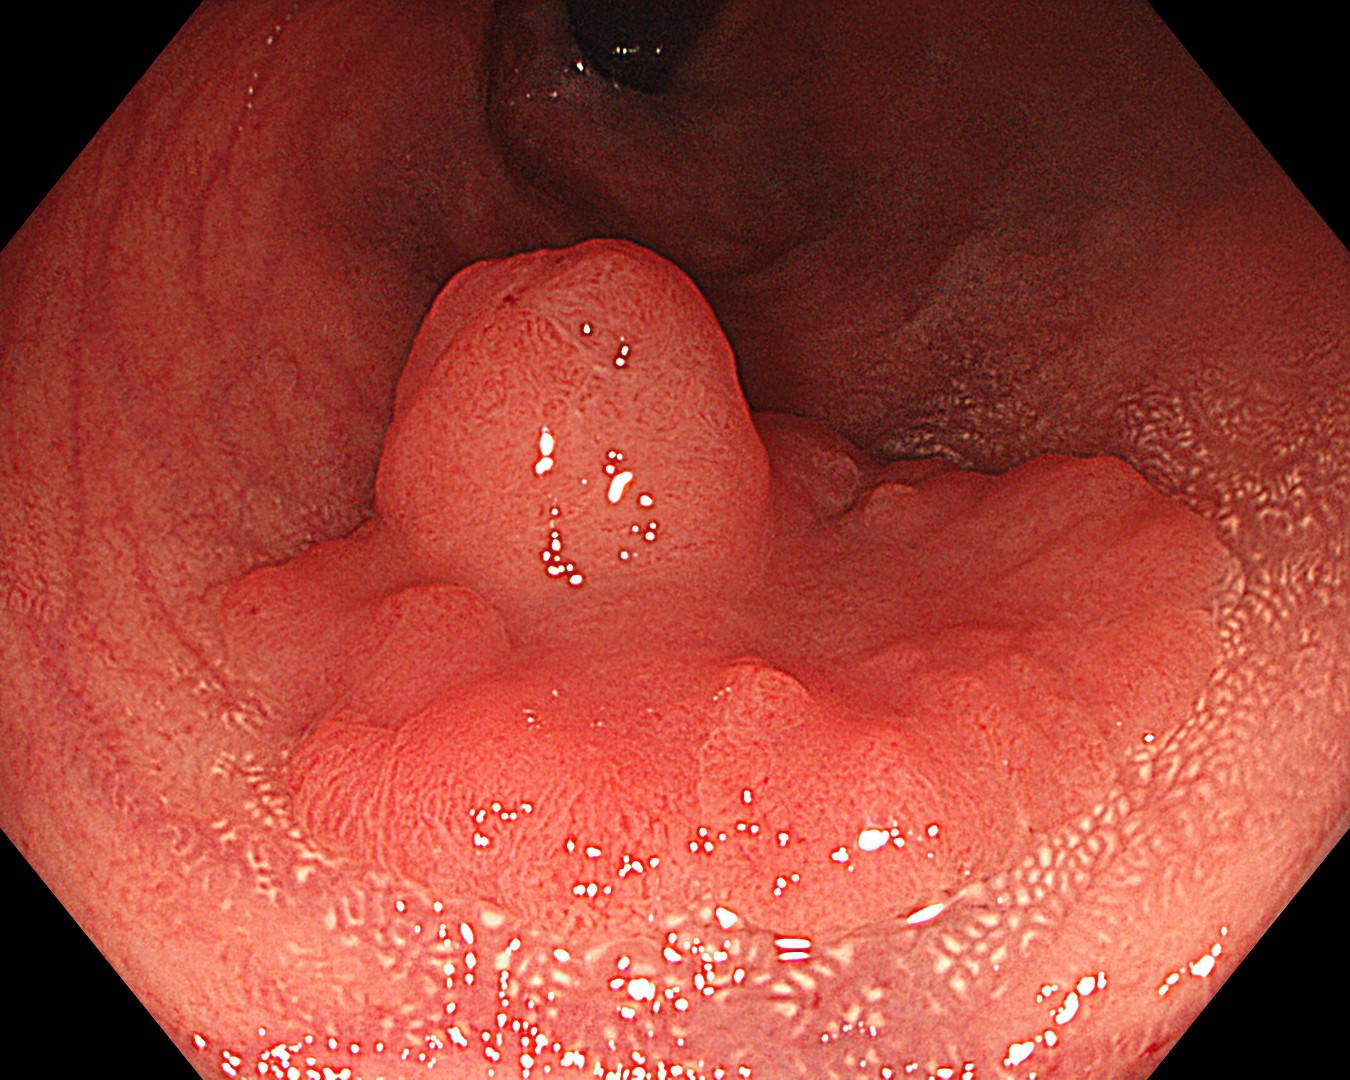

• 白色光観察②(近景)

強調設定:A8

図2

反転操作で病変口側からも白色近接観察を行った。平坦隆起部の表面にわずかな陥凹が認識された。